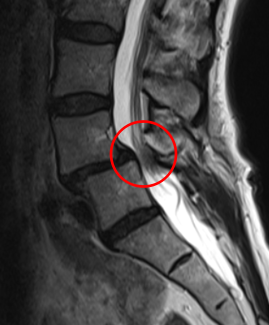

治療前

┃検査・診断

腰椎MRIを確認したところ、赤い枠で示されているL4/5 腰部脊柱管狭窄症、すべり症が見られました。特にL4/5脊柱管狭窄症に強く狭窄を認めました。

またこの腰部脊柱管狭窄症は、腰部すべり症が原因であると考えられます。